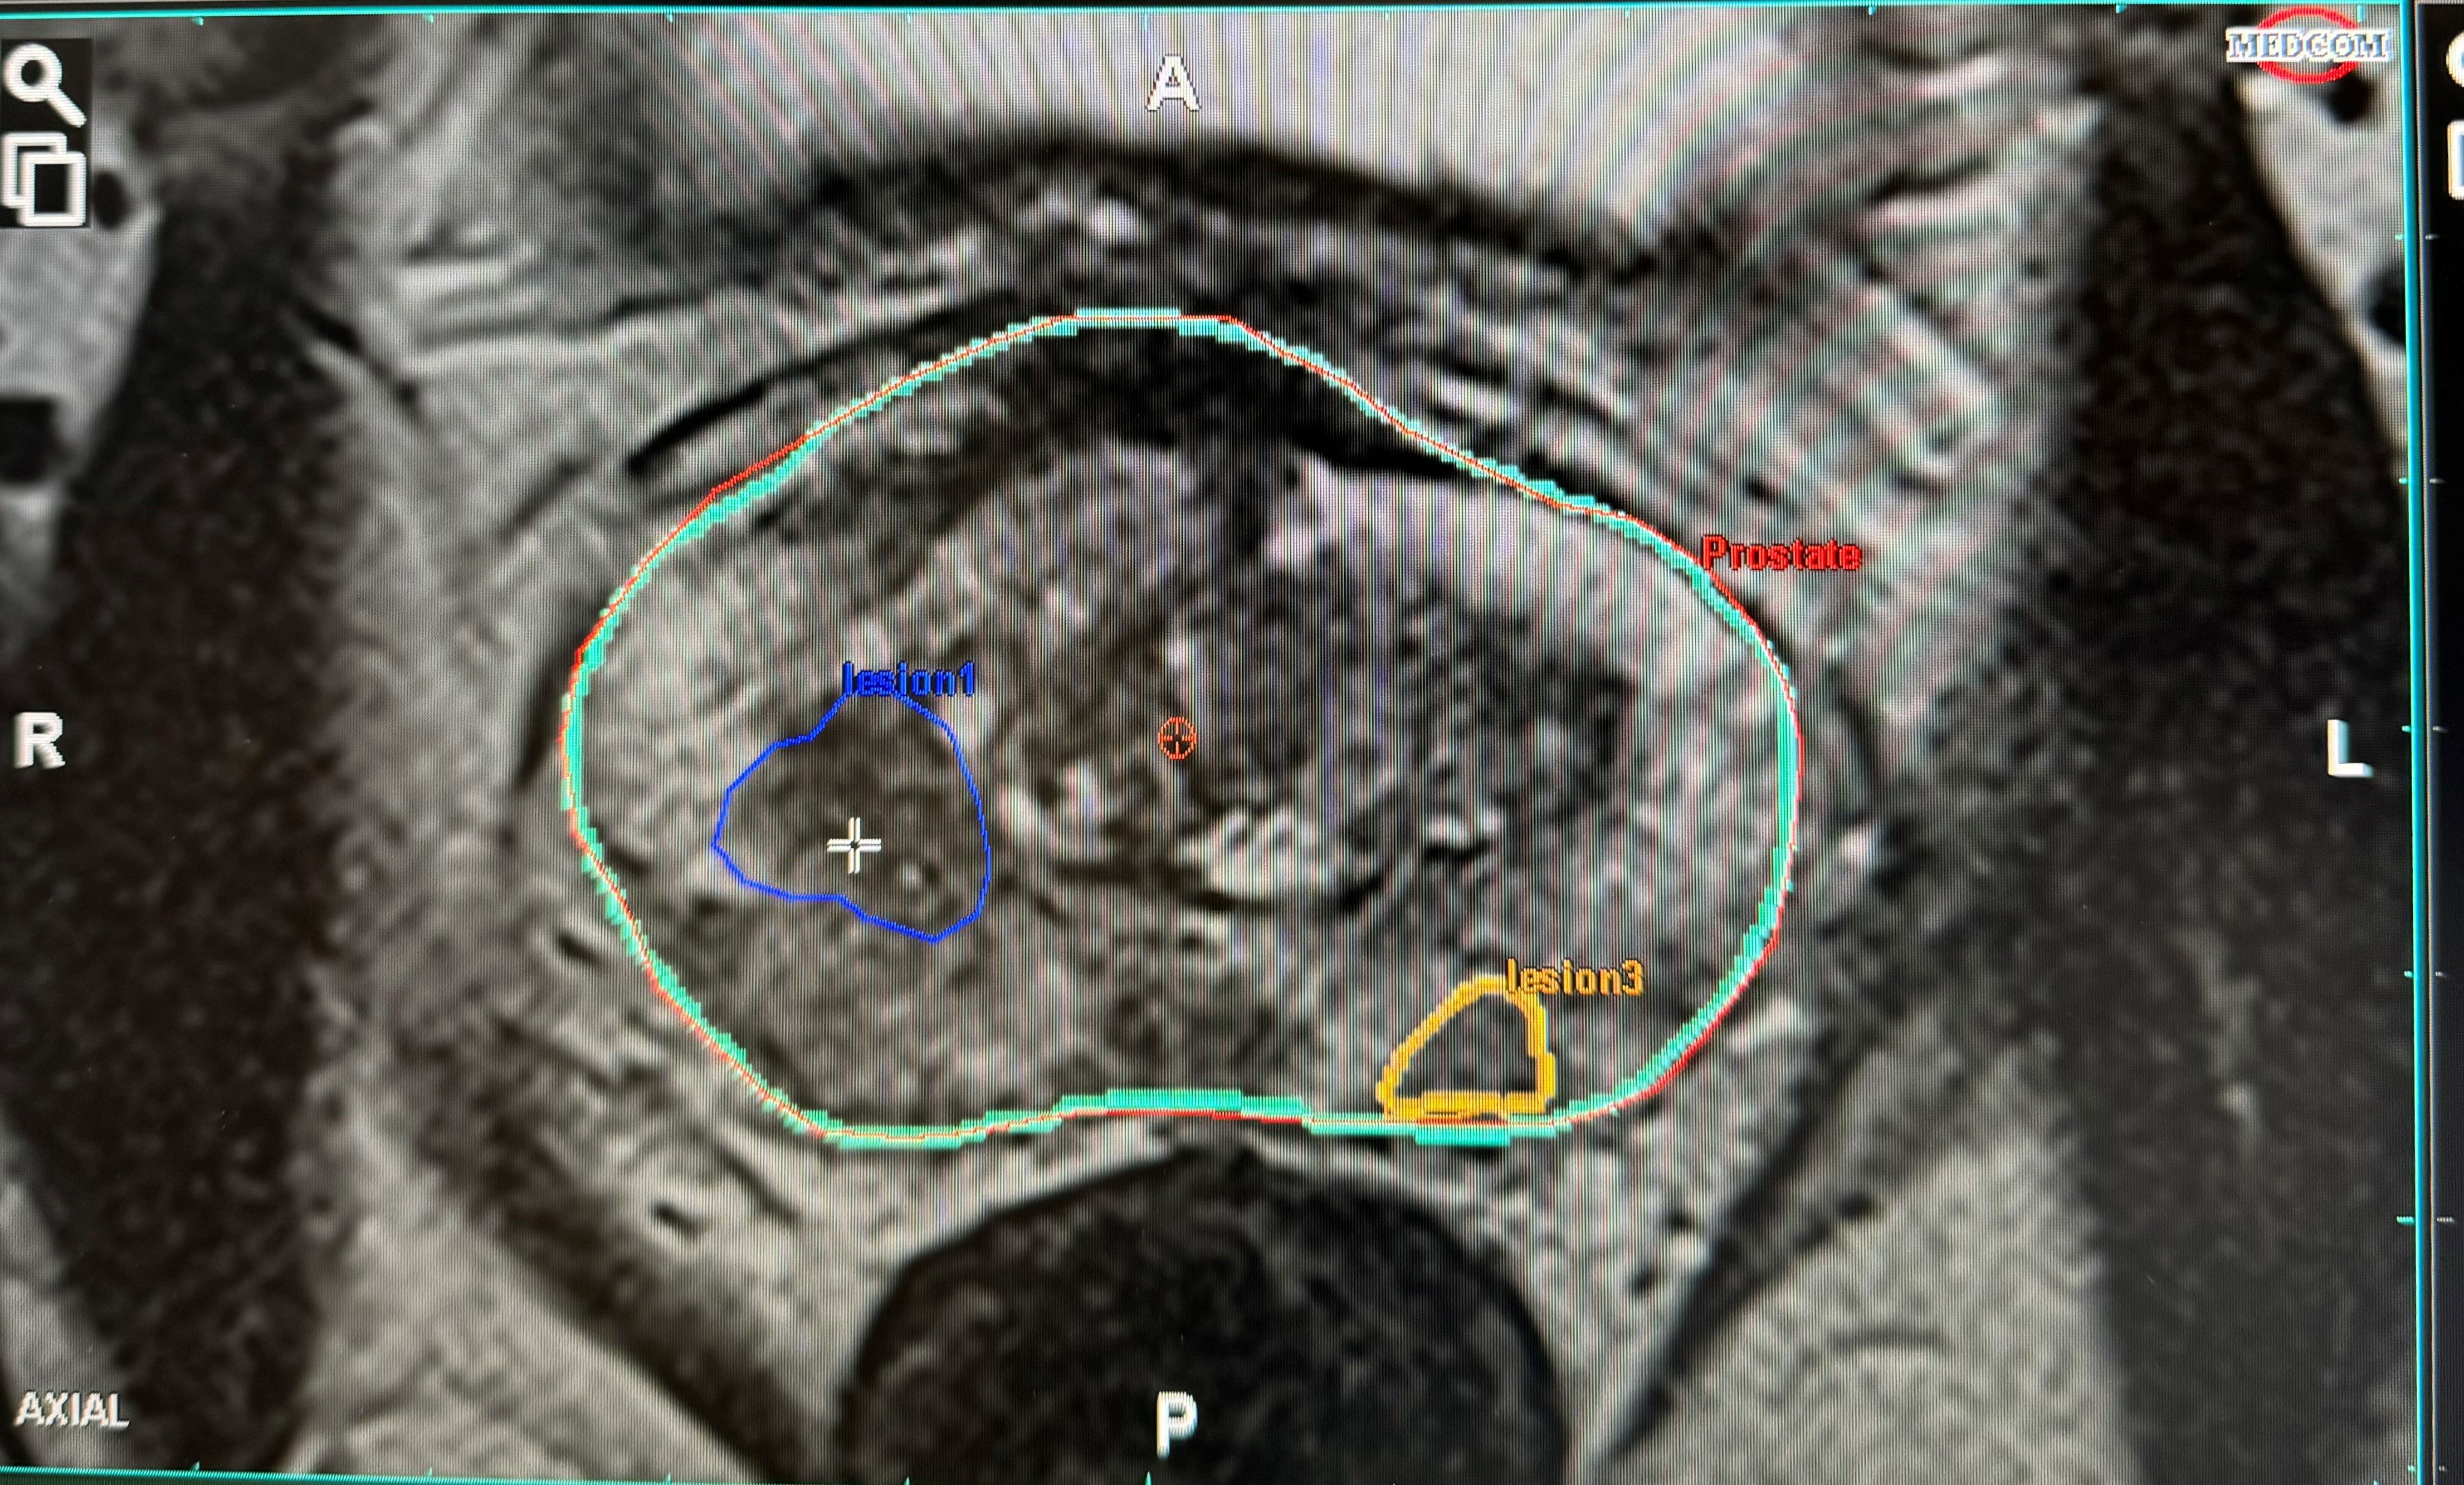

Die Fusionsbiopsie bezeichnet das Fusionieren zweier bildgebender Verfahren unter Zunahme der KI-gesteuerten mpMRT Bilder und eines hochauflösenden Ultraschalls zur gezielten Biopsie (Gewebeprobenentnahme) der Prostata.

Nach der Anfertigung Ihres mpMRTs der Prostata lesen wir die gewonnenen Bilder in eine KI-gesteuerte Planungssoftware ein. Hierbei fokussieren wir uns auf die korrekte Kontur Ihrer Prostata, Ihrer Harnröhre und dem Areal, welches von Ihrem Radiologen, als auch von künstlicher Intelligenz als auffällig beschrieben wurde. Diese angefertigte Kontur wird dann in das Ultraschallgerät vor Ihrer Biopsie übertragen. Mit Hilfe dieser Konturen sind wir in der Lage, auch kleinste auffällige Areale gezielt zu biopsieren.

Sie profitieren durch dieses modernste Verfahren von sehr sicheren und äußerst präzisen neuesten Untersuchungsmethoden zur Tumorentdeckung und –charakterisierung. Unsere Partner in der Radiologie greifen auf ein neuartiges und KI-unterstütztes Bildgebungsverfahren der multiparametrischen Magnetresonanztomographie der Prostata (auch mpMRT der Prostata) zurück. Hierbei handelt es sich um die verlässlichste Diagnosemöglichkeit zur Vorsorge, bei Verdacht auf oder bei bestehendem Prostatakrebs. Sie kann uns mit einer Sicherheit von über 90 Prozent den – wenn vorhanden – aggressivsten Tumorherd aufzeigen, welcher uns im Befund strukturiert und graphisch dargestellt übermittelt wird.

Auf Grundlage dieser Bildgebung können wir eine gezielte Gewebentnahme (Biopsie) durchführen. Dies geschieht mittels einer moderner, computergestützter Bildfusion – hierbei werden die mpMRT Bilder und Ultraschallbilder, welche wir für die Biopsie erzeugen, übereinander gelegt (Fusion). Die Biopsienadel kann somit bei der Gewebeentnahme genau auf den Tumor ausgerichtet werden und so die Treffsicherheit um ein vielfaches maximieren.